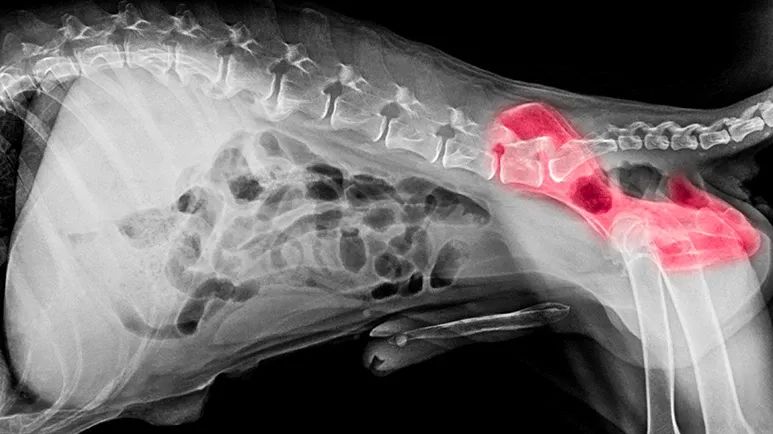

In a dog with healthy hips, the ball (the head of the femur) at the top of the leg bone fits perfectly into the socket. In animals with CHD, the less-than-perfect fit causes the bones to separate. This separation is the result of abnormal joint structure coupled with weak muscles, ligaments and connective tissue that support the joints.

The result is a joint that chafes and grinds rather than slides smoothly during movement. Often the body tries to compensate for the poorly fitting joint by producing hard, bony material in and around it to try to stabilize it. This alteration can have the opposite effect, creating an even more unnatural fit.

A dog is diagnosed with CHD if the ball and socket hip joint is malformed, causing separation of the two bones of the joint. In most cases, the socket is not deep enough for the ball to fit snugly into place.

Diagnosis is typically made either because a dog is showing symptoms, or as the result of a standard hip exam. Your veterinarian will perform a complete physical exam and take x-rays. He or she may also be able to feel looseness in your dog's hip joint and note pain when a rear leg is extended or flexed.